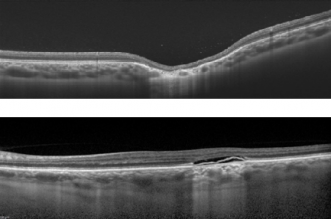

- Optical Coherence Tomography (OCT): In 2015, Wong et al. [42] proposed a classification of TM into two types according to the pattern of abnormality on OCT. In both types, there is attenuation of outer retinal structures (explained by RPE thinning and photoreceptor loss that can be attributed to several developmental defects [10] [11]) with an increased signal transmission along the choroid and conservation of inner layers.

- Type 1 include lesions that show attenuation of interdigitation zone and ellipsoid zone without outer retinal cavitation.

- Type 2 show loss of ellipsoid and interdigitation zones as well as thinning of the outer nuclear layer associated with outer retinal cavitation. Inner choroidal excavation may be present or absent[42][43].

- Type 3 lesions have been suggested as an additional category defined by excavated inner layers, retinal thinning, inner retinal hyper-reflective spaces, and no subretinal cleft [43]. Three cases of type 3 lesions have reported the presence of subretinal fluid.[44]

- Wong et al.[42] postulated Type 1 lesions evolve into Type 2 ones over several decades, although this has been refuted by Shirley et al.[3], asserting that the difference is phenotypical rather than temporal[42]. Rickmann et al. also found that there was no age difference between patients with Type 1 and Type 2 lesions, and type 2 TM can also occur in young patients.[45]

- Light and Liu proposed a type 4 morphology, reporting a case in which the foveal portion showed disruption of the ellipsoid zone without outer retinal cavitation, while the temporal tail had a preservation of the ellipsoid zone and inner choroidal excavation. [46]